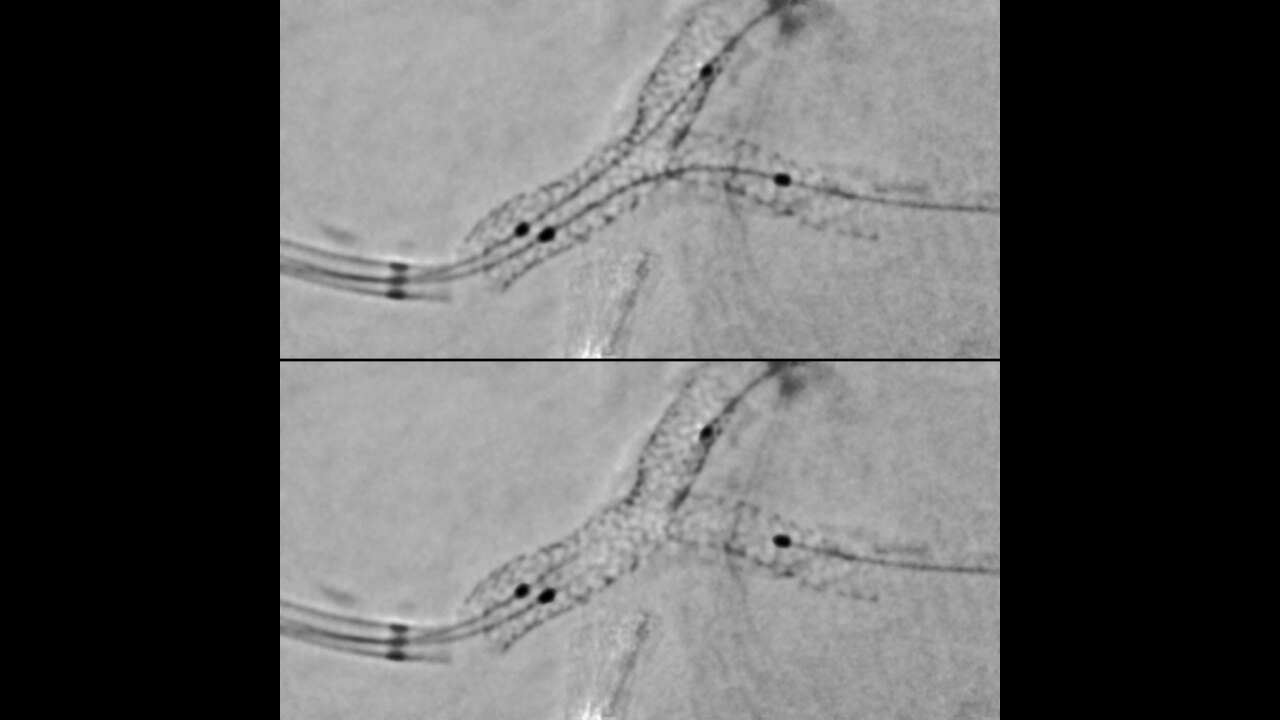

Guide

Augmented 2D image guidance

Help to increase positioning accuracy and confidence in multiple stent positioning.

Enhance the visibility of both stents in a bifurcation thanks to our improved StentViz algorithm.